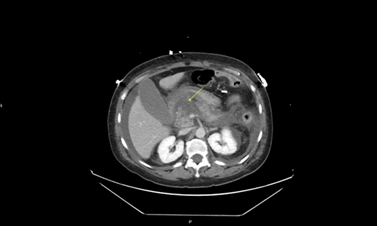

clinical condition and worsening lactic acidosis, repeat STAT CT abdomen and

pelvis was performed, which showed necrotizing pancreatitis (Figure 2),

large loculated ascites and bilateral pleural effusion with lower lobe

atelectasis.

Figure 2: CT scan showing pancreatic

necrosis (Yellow arrow)